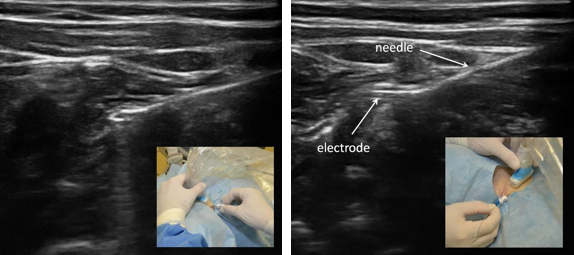

导线的放置采用超声技术,行平面内视觉跟踪18G×75mmTuohy尖头针。

根据制造商建议,选择理想的导线放置方法,超声下可见针穿越筋膜平面深到胸锁乳突肌(SCM)到达前斜角肌(ASM)表面。

在超声引导下,带生理盐水推注的针通过1mm的皮肤切口进入,直至尖端到达颈根部的颈内静脉和颈动脉附近,推注盐水出针。通过水分离术扩大ASM和SCM组织平面之间的距离及预期膈神经位置。当针到达位置后,经针头尖端置入导线,超声引导下退针留导线。导线被连接到PEPNS控制台获得膈神经信号。